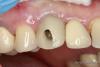

an_ver Опубликовано 10 августа, 2013 Поделиться Опубликовано 10 августа, 2013 Ранее был удален 1,3 так как устал быть в связке с имплантом на 1.2...короче скол ниже уровня десны на 3-4 мм. Убрали, поставили 4,2*13 АльфаБио (SPI).Временный абатмент,коронка.Сформировали десну, инд.абатмент (Церек) платформа немецкая, коронка пресс.Все.... 7 Ссылка на комментарий

an_ver Опубликовано 10 августа, 2013 Автор Поделиться Опубликовано 10 августа, 2013 Не совсем верная ортопедическая позиция винта(имхо) , без шаблона ставили ? На 12 , 22 ваши реставрации ?Если внимательно читали то...еще раз))) Ранее был удален 1,3 так как устал быть в связке с имплантом на 1.2. разьединили1.2 и1.3...1.3 удалили.На 1.2 коронка на импланте осталась,делали давно, имплант не знаю какой..похож на АльфаБио (ARRP), 2.2 из той же темы.Не мои работы.Не совсем верная позиция винта ортопедическая...может быть..Наш ваш взгляд какая должна быть? Ссылка на комментарий